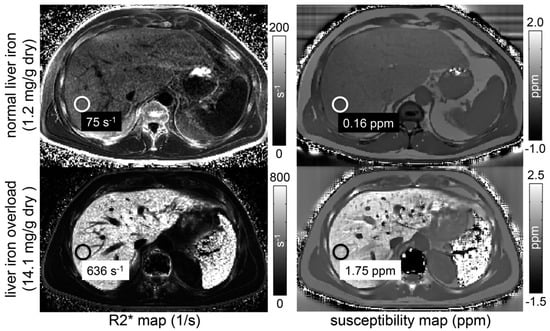

2.2.4. Susceptibility-Weighted Imaging (SWI) and Quantitative Susceptibility Mapping (QSM)

- Sharma, S.D.; Fischer, R.; Schoennagel, B.P.; Nielsen, P.; Kooijman, H.; Yamamura, J.; Adam, G.; Bannas, P.; Hernando, D.; Reeder, S.B. MRI-based quantitative susceptibility mapping (QSM) and R2* mapping of liver iron overload: Comparison with SQUID-based biomagnetic liver susceptometry. Magn. Reson. Med. 2017, 78, 264–270. [Google Scholar] [CrossRef]

- Sharma, S.D.; Hernando, D.; Horng, D.E.; Reeder, S.B. Quantitative susceptibility mapping in the abdomen as an imaging biomarker of hepatic iron overload. Magn. Reson. Med. 2015, 74, 673–683. [Google Scholar] [CrossRef] [PubMed]